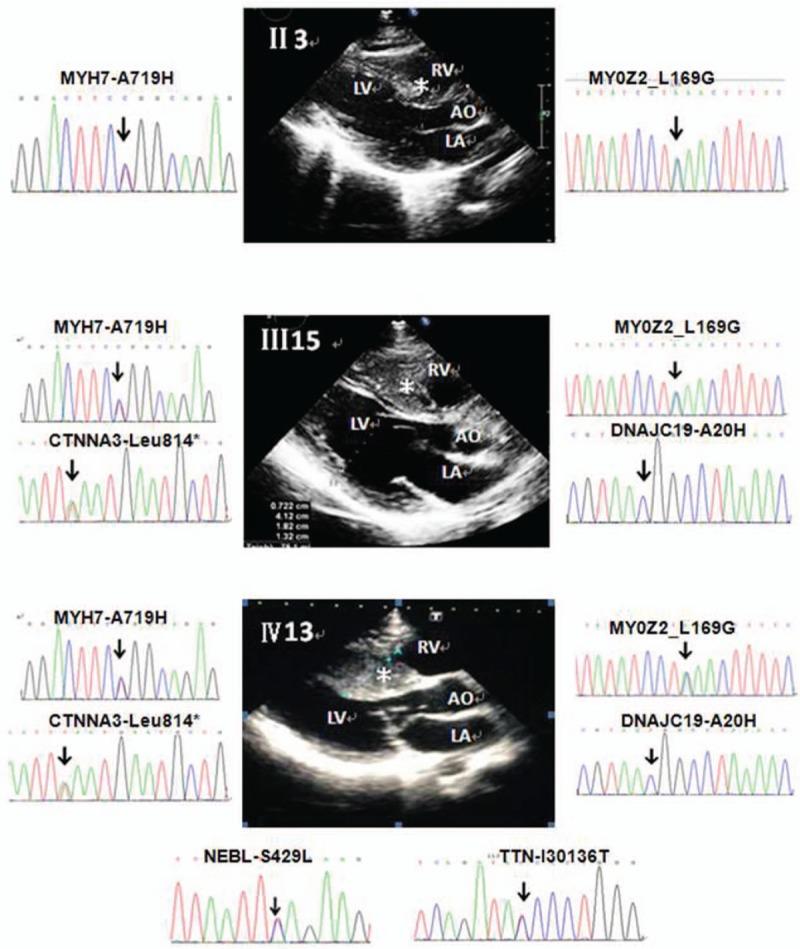

Hypertrophic cardiomyopathy (HCM) is the most common heritable heart disease. The genetic anticipation of HCM and its associated etiology, sudden cardiac death (SCD), remains unclear. The aim of this study was to investigate the mechanism underlying the genetic anticipation of HCM and associated SCD.An HCM family including 5 generations and 74 members was studied. Two-dimensional echocardiography was performed to diagnose HCM. The age of onset of HCM was defined as the age at first diagnosis according to hospital records. The information on SCD was confirmed by verification by ≥2 family members and a review of hospital records. Whole-genome sequencing was performed on 4 HCM subjects and 1 healthy control in the family. The identified mutations were screened in all available family members and 216 unrelated healthy controls by Sanger sequencing.The median ages of onset of HCM were 63.5, 38.5, and 18.0 years in members of the second, third, and fourth generations of the family, respectively, and the differences between the generations were significant (P < 0.001). The age at SCD also decreased with each subsequent generation (P < 0.05). In particular, among the third-generation family members, SCD occurred between 30 and 40 years of age at approximately 8 AM, whereas among the fourth-generation family members, all 5 males who experienced SCD were 16 years of age and died at approximately 8 AM. The sarcomere gene mutations MYH7-A719H and MYOZ2-L169G were detected in the HCM individuals in this pedigree. Increases in the number of mutations and the frequency of multiple gene mutations were observed in the younger generations. Moreover, a structural variant was present in the HCM phenotype-positive subjects but was absent in the HCM phenotype-negative subjects.HCM may exhibit genetic anticipation, with a decreased age of onset and increased severity in successive generations. Multiple gene mutations may contribute to genetic anticipation in HCM and thus may be of prognostic value.

肥厚型心肌病(HCM)是最常见的遗传性心脏病。HCM的遗传早现及其相关病因——心源性猝死(SCD),目前仍不清楚。本研究的目的是探讨HCM遗传早现及相关SCD的潜在机制。对一个包括5代74名成员的HCM家系进行了研究。采用二维超声心动图诊断HCM。根据医院记录,将HCM的发病年龄定义为首次诊断时的年龄。SCD信息经≥2名家庭成员核实及查阅医院记录后得以确认。对该家系中的4名HCM患者和1名健康对照进行了全基因组测序。通过Sanger测序在所有可用的家庭成员和216名无关健康对照中筛选出已鉴定的突变。该家系第二代、第三代和第四代成员HCM的发病年龄中位数分别为63.5岁、38.5岁和18.0岁,代际差异具有统计学意义(P<0.001)。SCD的年龄也随代际增加而降低(P<0.05)。特别是,在第三代家庭成员中,SCD发生在30至40岁之间,时间约为上午8点,而在第四代家庭成员中,所有5名发生SCD的男性均为16岁,且均在上午8点左右死亡。在该家系的HCM个体中检测到肌节基因突变MYH7-A719H和MYOZ2-L169G。在较年轻的世代中观察到突变数量增加和多基因突变频率增加。此外,HCM表型阳性的受试者中存在一种结构变异,而HCM表型阴性的受试者中不存在。HCM可能表现出遗传早现,发病年龄降低且连续几代病情严重程度增加。多基因突变可能导致HCM的遗传早现,因此可能具有预后价值。